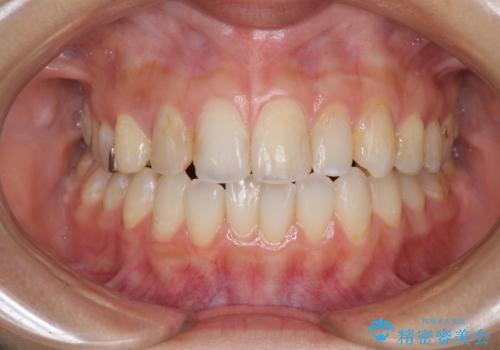

後戻りを治したい 骨格的なズレの大きい方のインビザライン矯正

- 中学生の時に矯正治療をしたものの、後戻りを気にして来院された患者様です。

骨格的に下顎が右側に変位しているため、左右の咬み合わせを理想的なものに改善することはできませんが、インビザラインにて歯列を整えることとしました。

骨格的なズレによる左右差は改善できませんでしたが、上下の正中を極力合わせるようにすることができました。